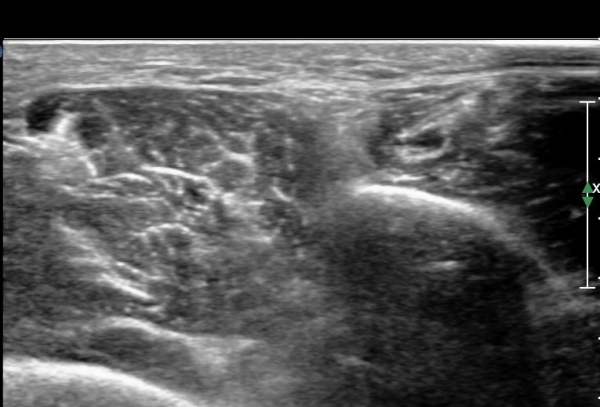

¸»´ÜÀ¸·Î °¥ ¼ö ·Ï ³¶Á¾ÀÌ Ä¿Áø°í õºñ°ñ½Å°æ ¾Ð¹ÚÀº ½ÉÇØÁø´Ù(»çÁø 8).